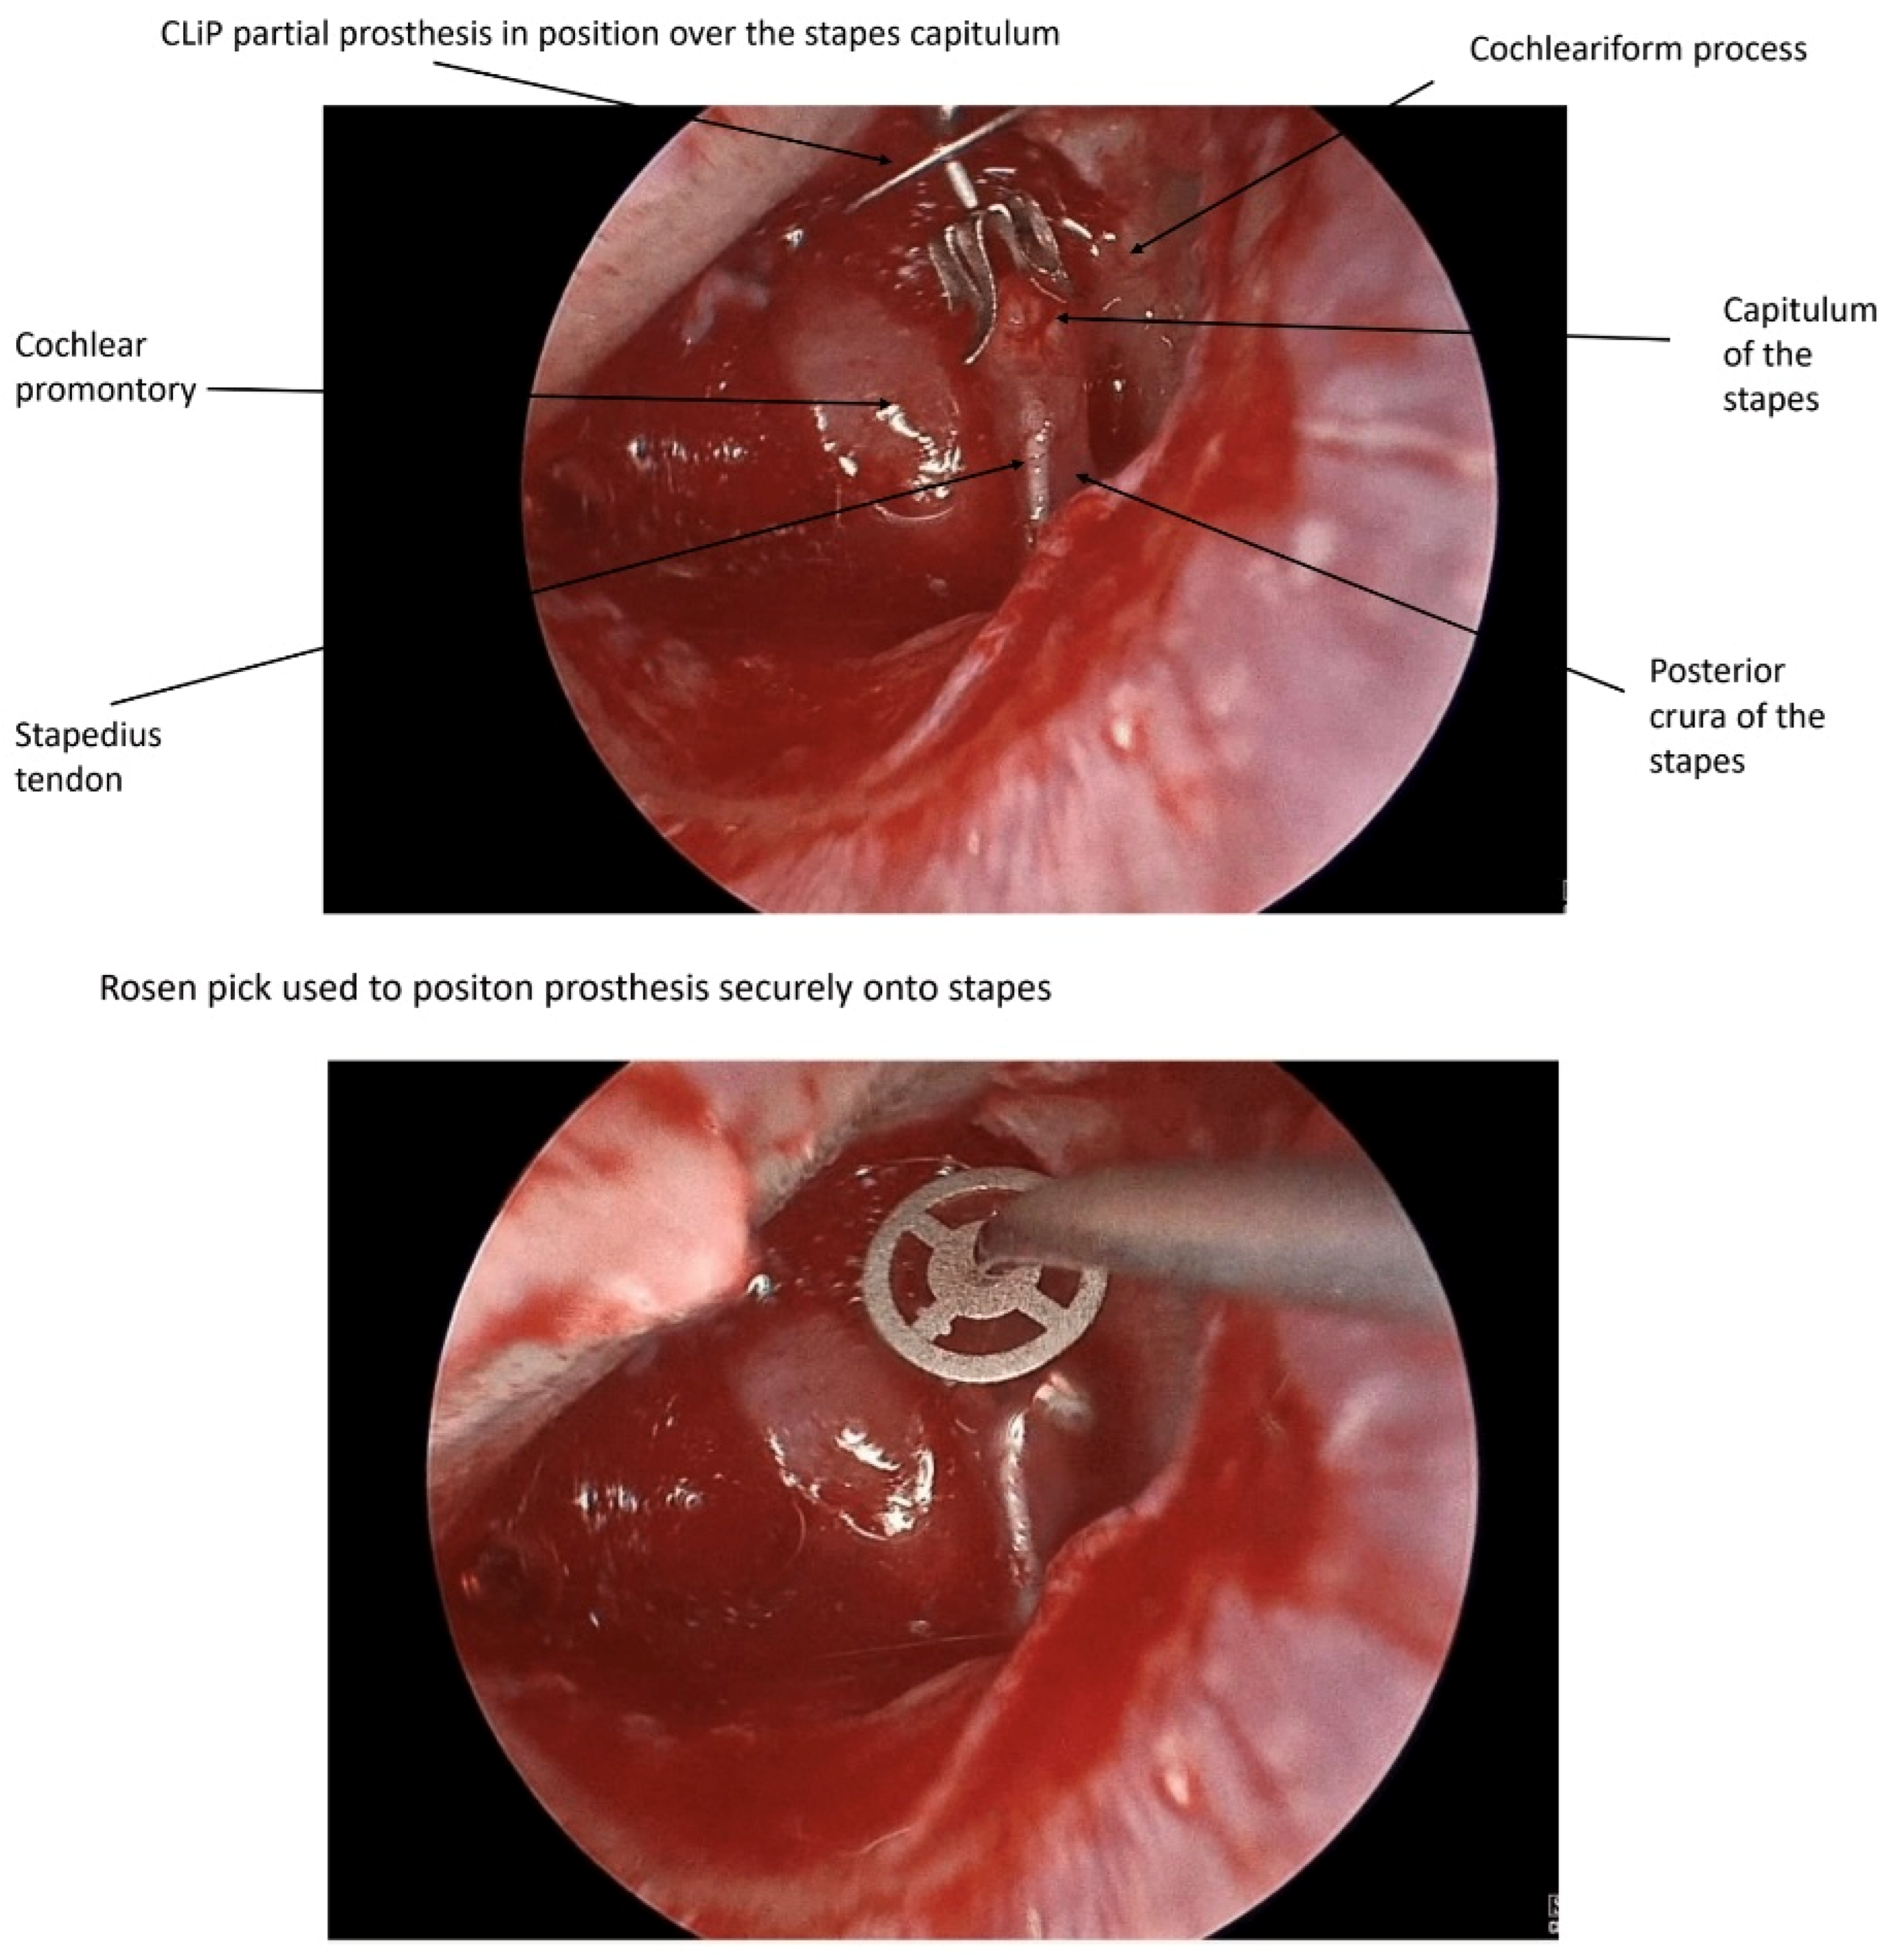

1. Introduction